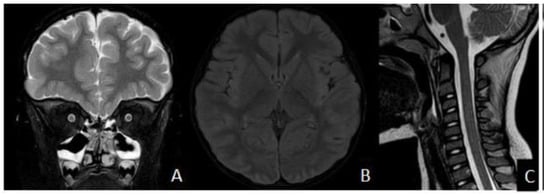

FLAIR Hyperintense Cortical Lesions in a 4-Year-Old Child with Myelin Oligodendrocyte Glycoprotein (MOG)-Associated Encephalitis and Seizures: A Case Report

2. Case Presentation